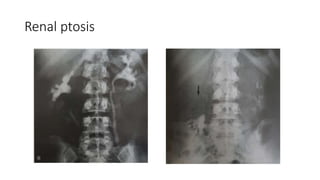

Erect film:

• Renal ptosis, bladder hernias, cystoscelces

Renal ptosis